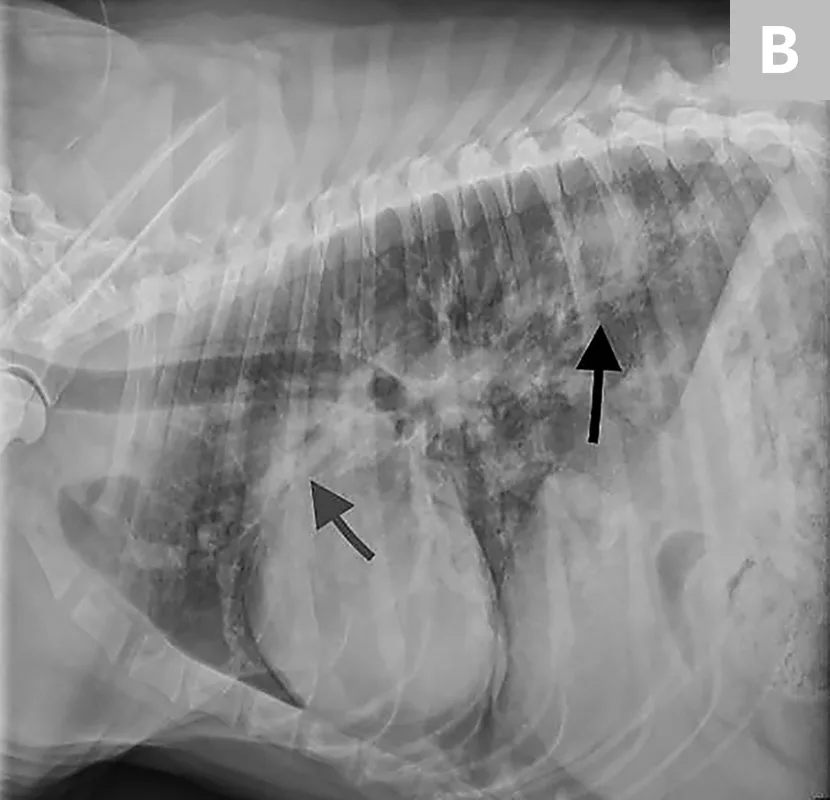

FIGURE 4

Echocardiogram of a dog with caval syndrome showing large worm burden (arrow) in the right ventricle, severe right ventricular hypertrophy, and septal flattening. Image courtesy of Clarke E. Atkins, DVM, DACVIM

When large numbers of worms mature over a short period of time, the right heart chambers and vena cava can become engorged with worms (ie, caval syndrome), leading to severe right-sided heart dysfunction, pulmonary hypertension, intravascular hemolysis, hemoglobinuria, disseminated intravascular coagulation, shock, and multiple organ failure (Figures 3 and 4).